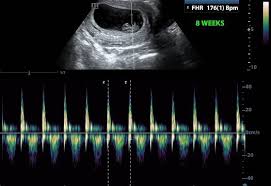

As far as i know the heartbeat should be visible by 65 weeks on ultrasound. Keep your fingers crossed for me guys. Gilbert Arizona 8 posts.

Baby measuring a bit small at 28 weeks. Baby Growth Behind at 8 Weeks Ultrasound - posted in PG after IVF. If theres a heartbeat at 9 weeks the probability of a miscarriage plummets and shell have greater reassurance that her pregnancy will continue.